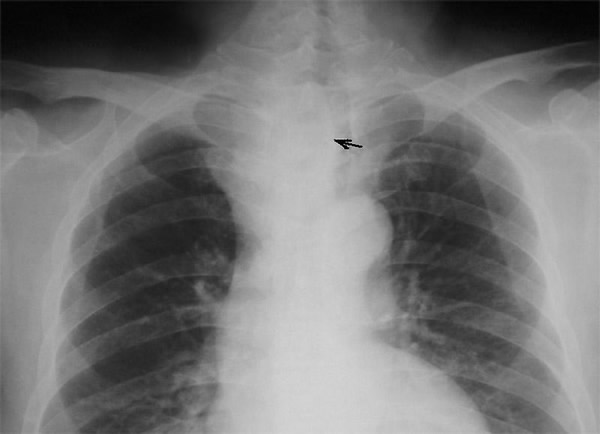

A 58-year-old Chinese man presented with a dry cough of three months’ duration. A chest x-ray at a local hospital revealed "a shadow in the superior mediastinum." A subsequent CT scan suggested "ectopic intrathoracic thyroid" (Figures 1 and 2). His physical examination revealed normal temperature and heart rate, without any signs of hyperthyroidism. Palpation of the neck revealed a non-tender, firm, fixed, and non-pulsatile 2 cm right inferior thyroid mass. A repeat chest x-ray confirmed a mass in the right anteromedial mediastinum, with smooth margins, tracheal compression, and deviation of the trachea to the left (Figure 3). Nuclear Tc99 thyroid scan revealed a cold nodule in the right inferior thyroid gland extending below the sternum (Figure 4). The values of total thyroxin 3 (TT3), total thyroxin 4 (TT4), free thyroxin 3 (FT3), free thyroxin 4 (FT4), and thyroid stimulating hormone (TSH) were all normal. Due to the suspicion of malignancy and to avoid the development of tracheomalacia, surgery was performed to remove the mass.